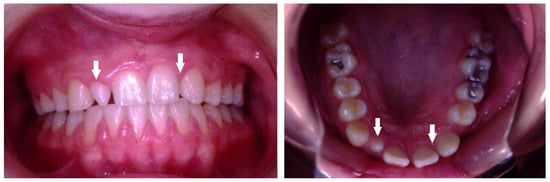

| Ectopic | Eruption of teeth not in their normal position. |